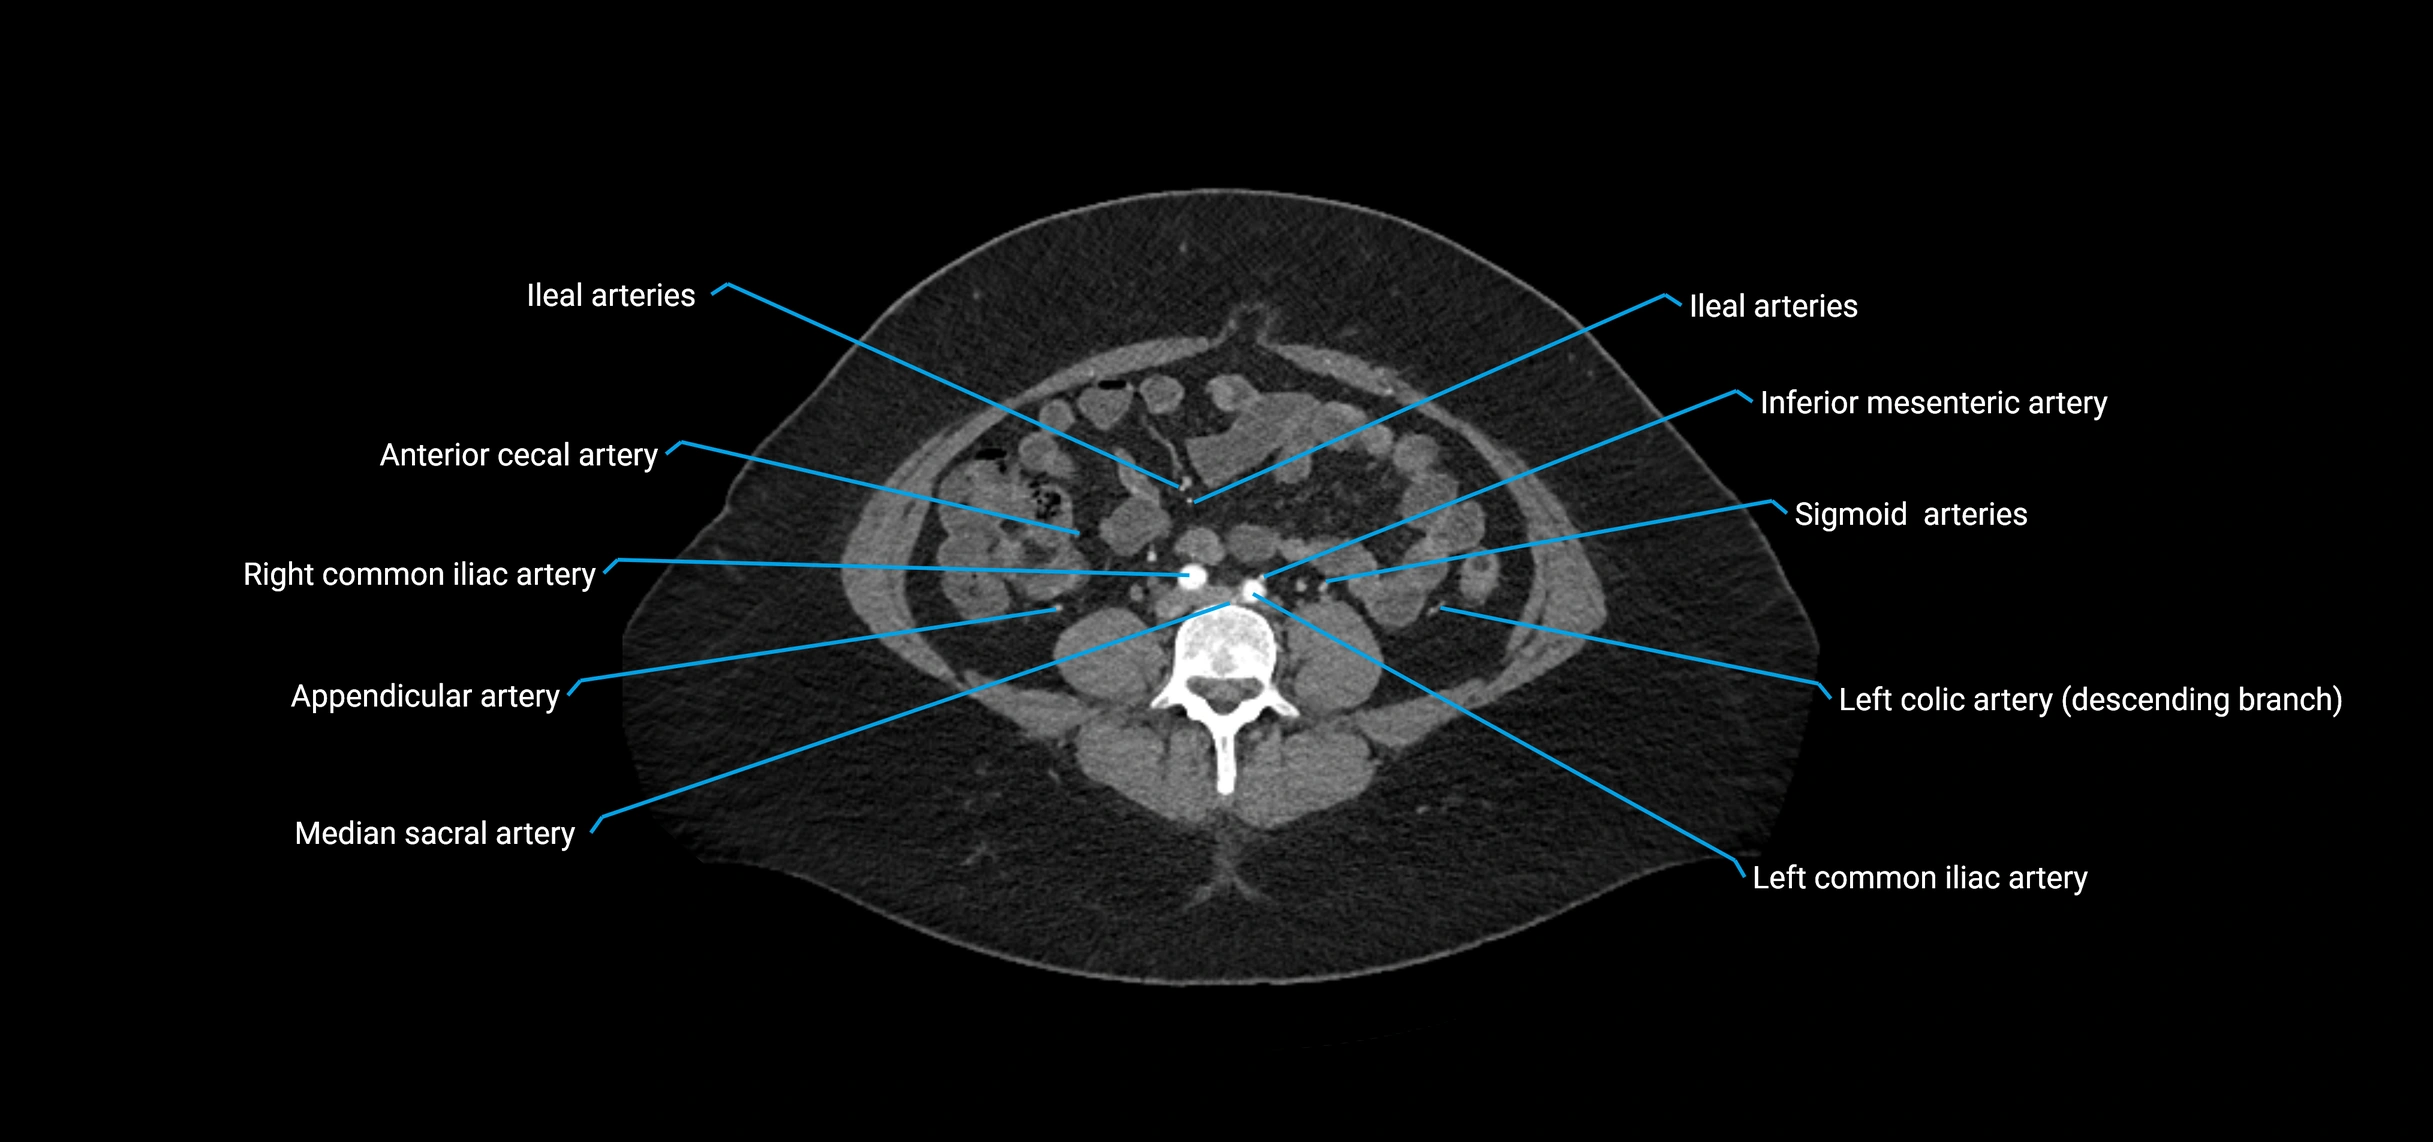

CT images

image

Contrast-enhanced CT (CTA):

• Gold standard for abdominal aortic imaging

• Provides excellent detail of lumen, wall, aneurysm, thrombus, and branch vessels

• Multiplanar and 3D reconstructions help in aneurysm measurement, stent graft planning, and dissection evaluation